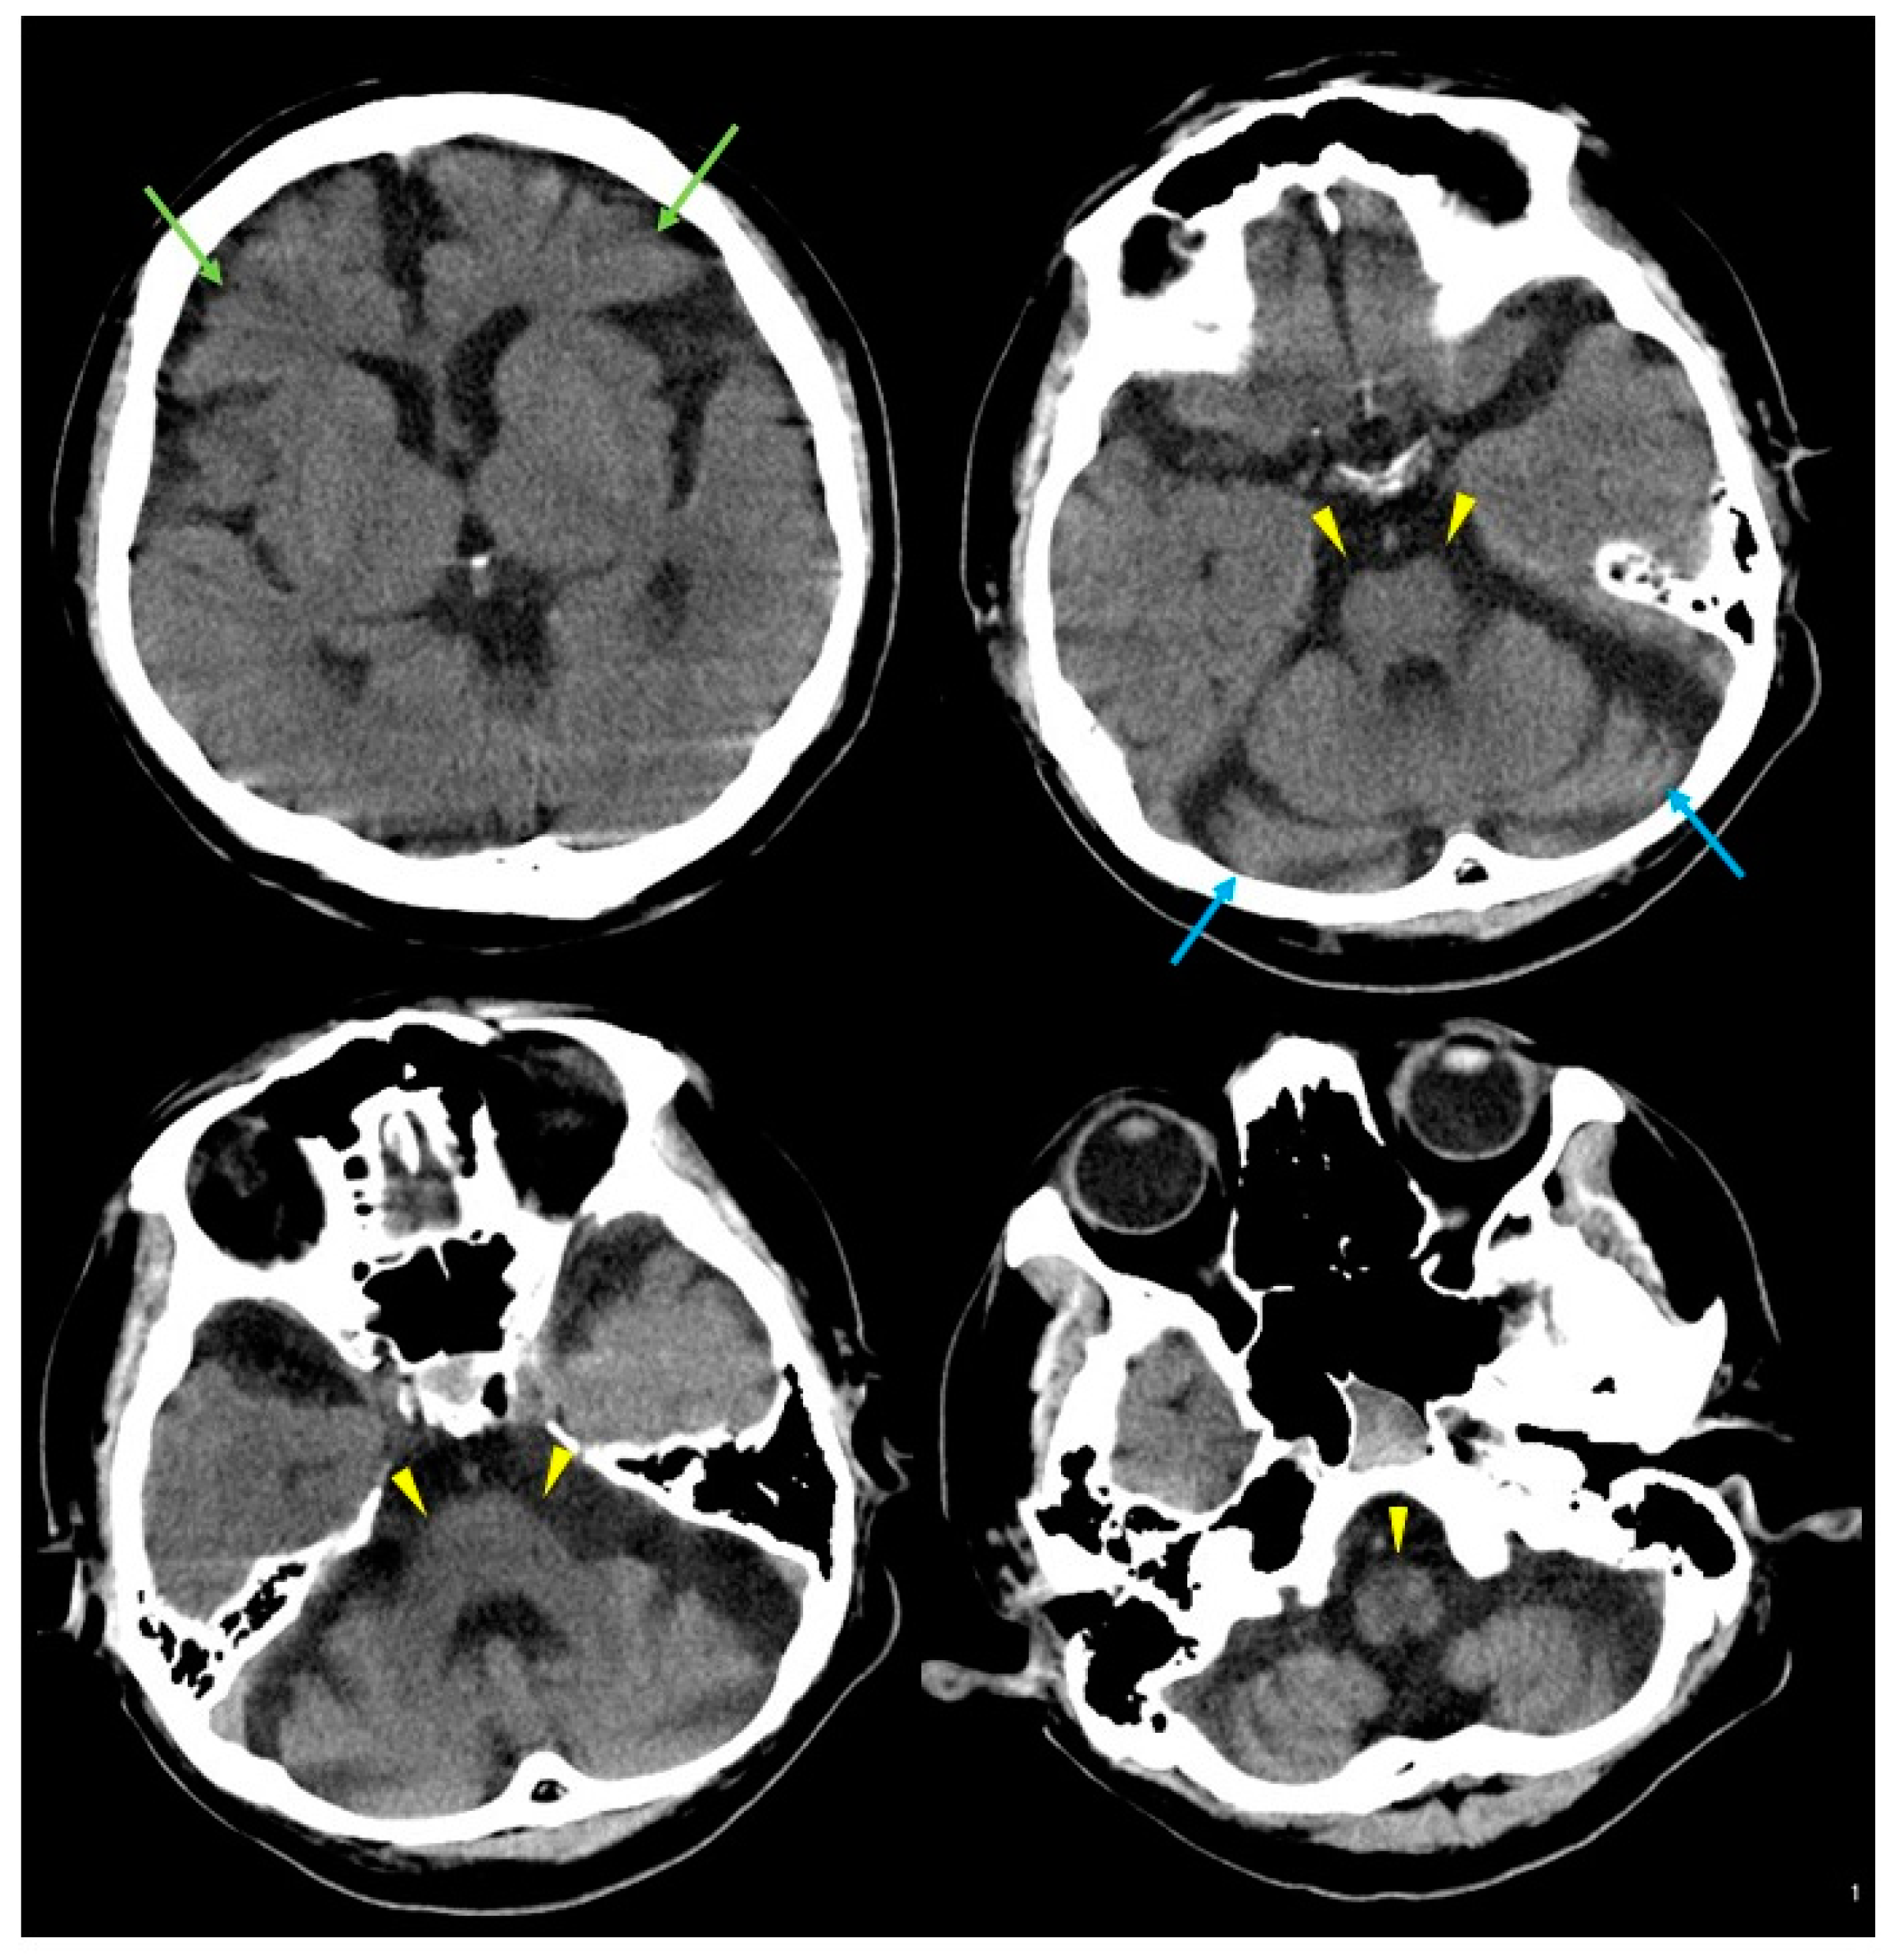

2. Case Presentation